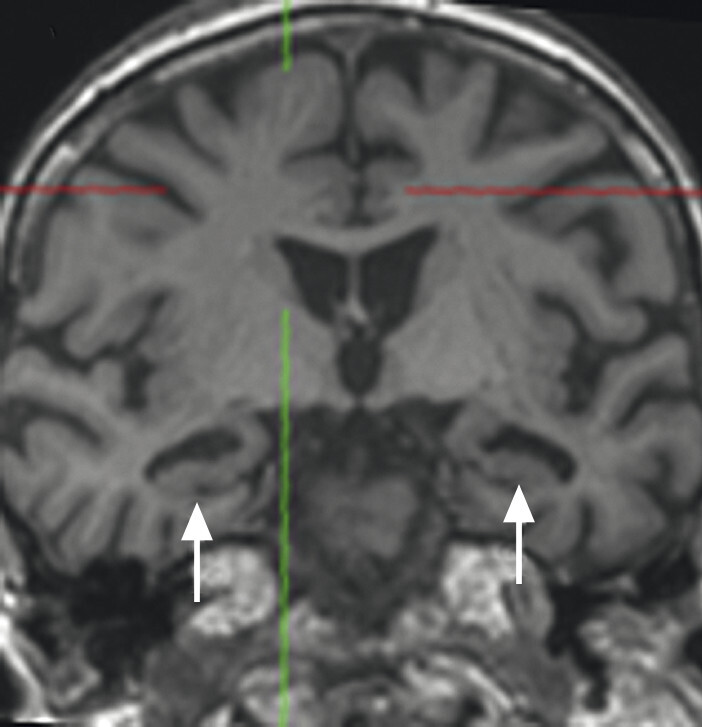

Abb. 69.10 Parkinson-Syndrome: Differenzialdiagnose progressive supranukleäre Parese mit Parkinson-Syndrom.

74-jähriger Patient mit linksbetontem Parkinson-Syndrom und aktuell deutlicher demenzieller Entwicklung mit exekutiver Störung und Zeitgitterstörung. In der T1w 3-D-MRT zeigt sich ein unauffälliges Mesenzephalon (a) mit einer normalen Midbrain/Pons-Ratio von 0,61 (kurzer Durchmesser des Mesenzephalons: 9,9 mm; kurzer Durchmesser des Pons: 16,1 mm, beide durch eine rote Linie dargestellt; b). Die automatisierte Ganzhirnvolumetrie (c) lässt außerdem ein anomales Hirnvolumen frontal bis parietal beidseits erkennen. In der 2 mm dünnen transversalen SWI-Schicht findet sich kein Schwalbenschwanzzeichen (d).

a T1w 3-D-MRT-Sequenz.

b T1w 3-D-MRT-Sequenz mit eingezeichneten Durchmessern.

c Ganzhirnvolumetrie.

d Transversale SWI.